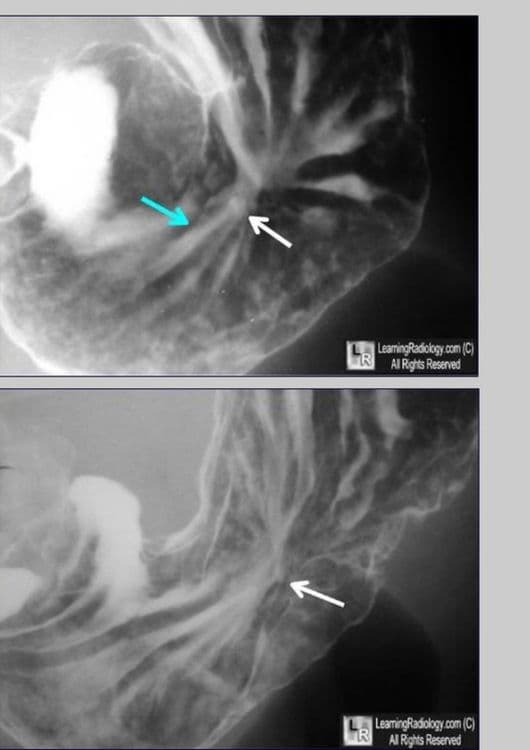

जसं विज्ञानाने प्रगती केली तसं अल्सर एक्स-रे मशीनद्वारेही पाहता येतो, हे डॉक्टरांच्या लक्षात आलं. पण अशी मशीन फक्त न्यू यॉर्क, लंडन अशा मोठ्या शहरांतच होती. इथल्या डॉक्टरांनी, त्यांच्या काही निरीक्षणांवरून, कामाचा ताण जास्त असलेल्या आणि मोठ्या प्रमाणावर धूम्रपान करणाऱ्या व्यावसायिकांना अल्सरचा त्रास होतो असा शोध लावला.